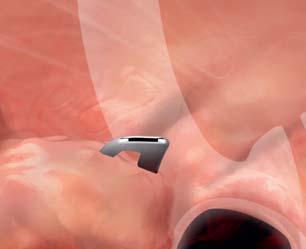

Using the Soft, Mega, Distal Transparent Cap to Remove Food Bolus